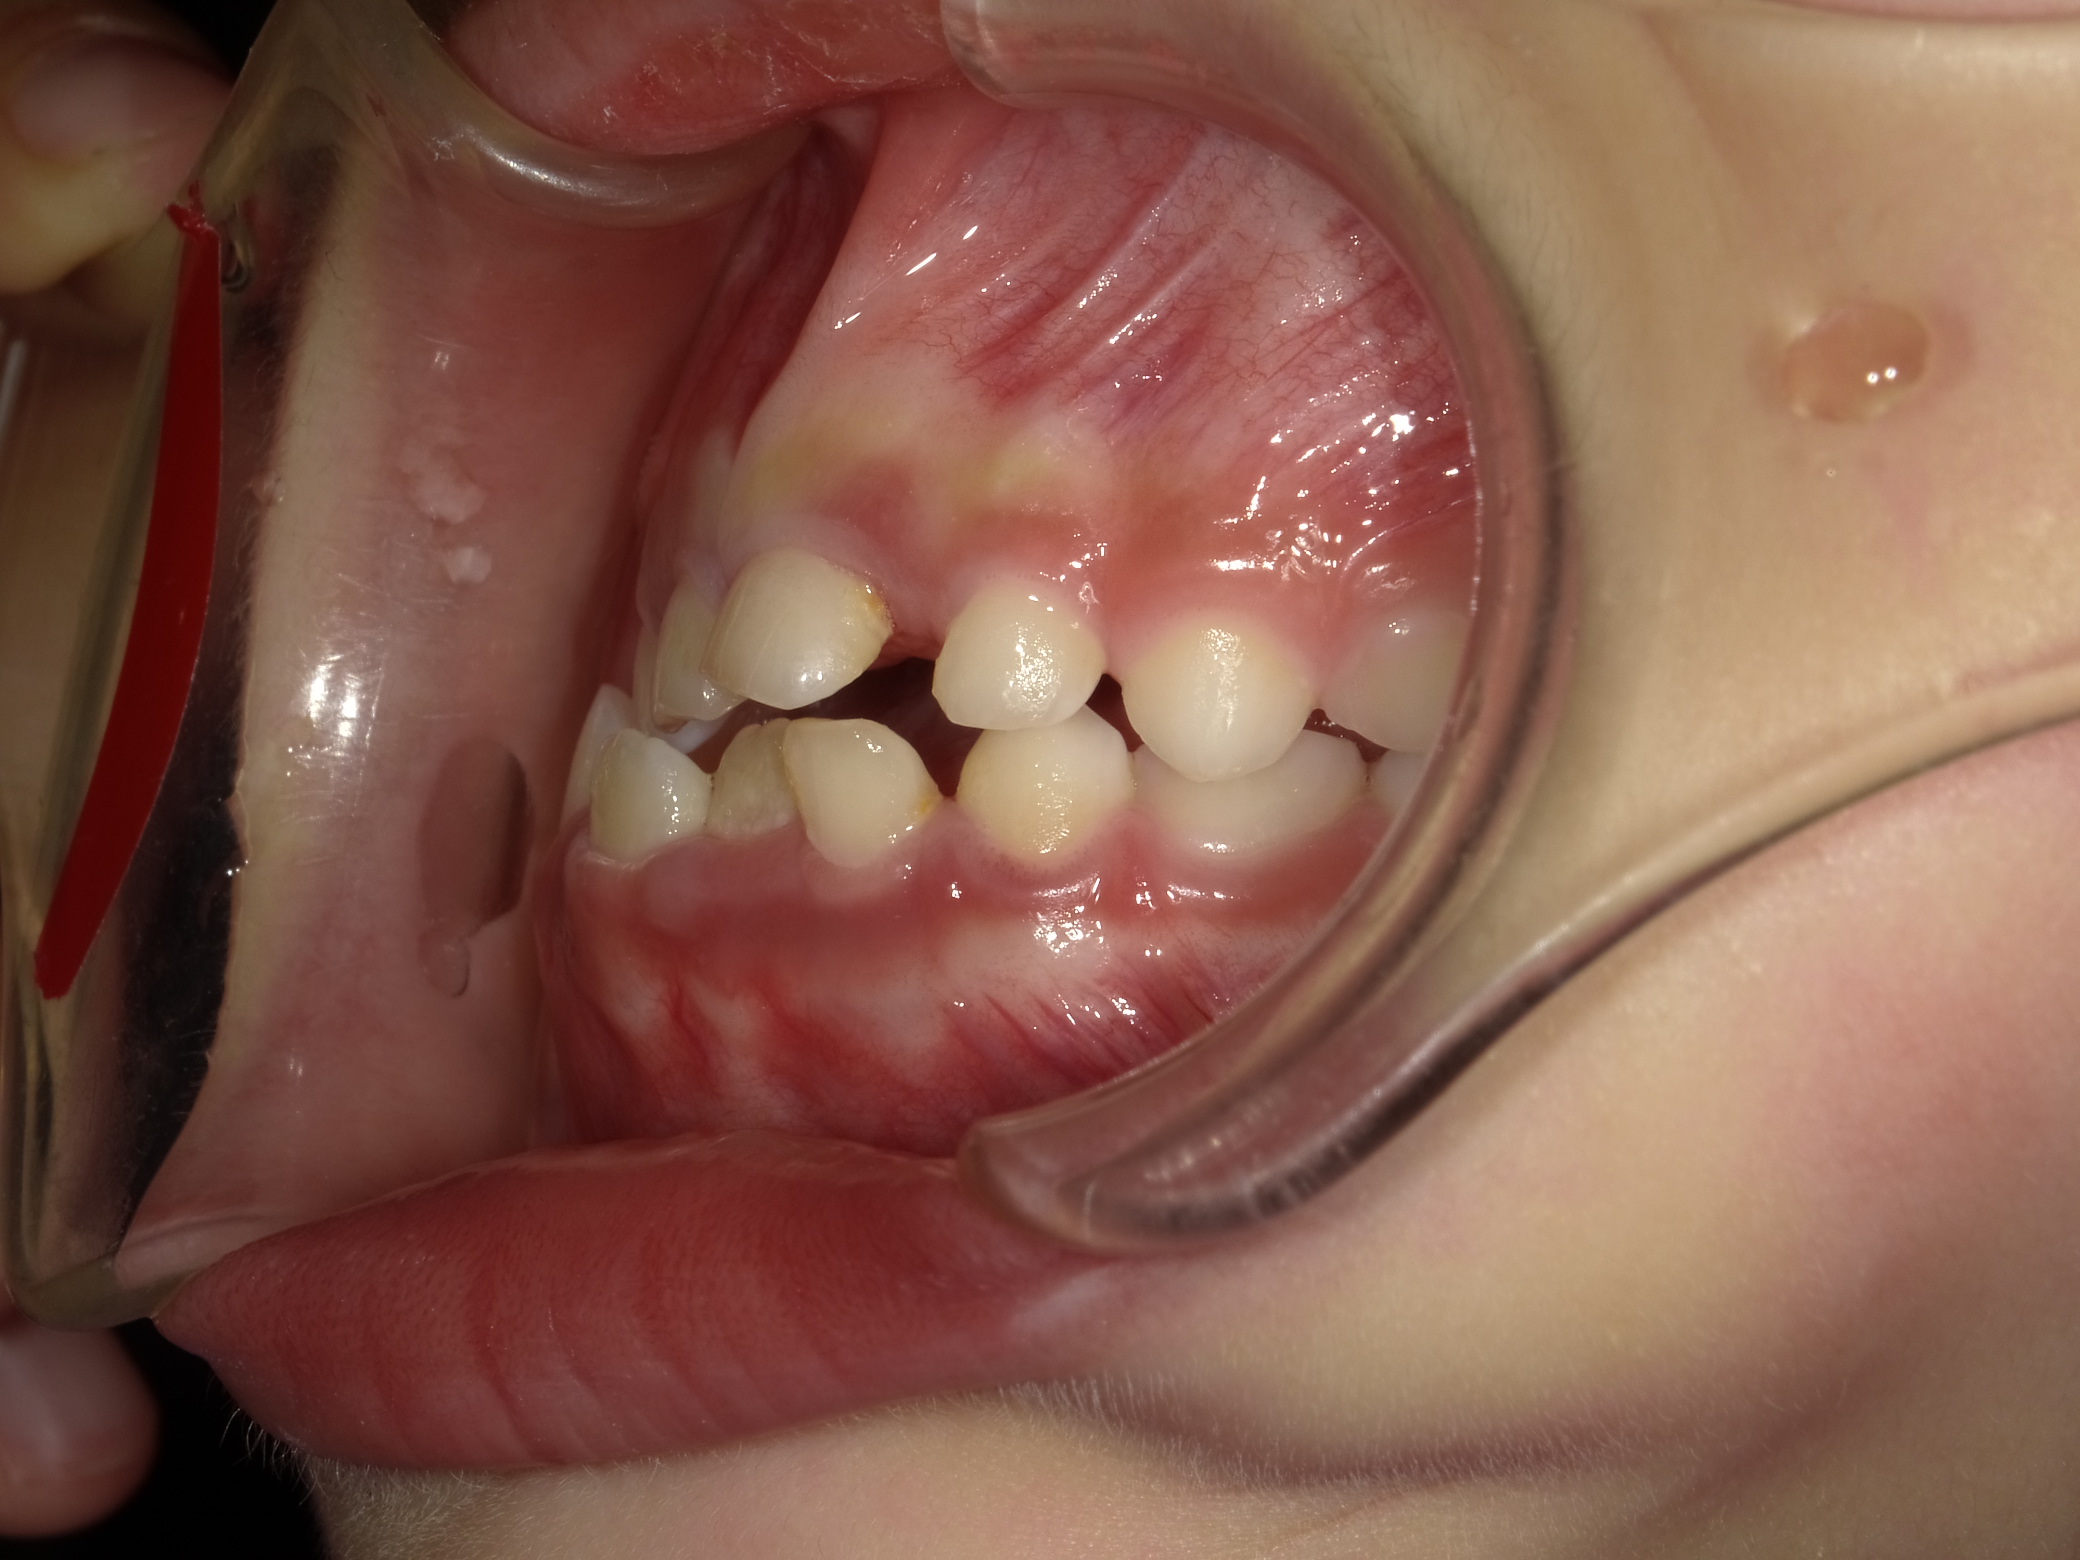

左横